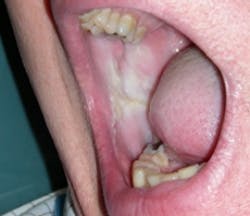

After completing your extraoral exam, you begin to inspect the lip tissues and the buccal mucosa. The tissues in the buccal mucosa areas appear thickened, keratinized, and somewhat striated (see Figure 1). Edward has extreme tissue damage along the occlusal plane and also in the lip area next to the wet line tissues. You alsoDiagnosis: Morsicatio buccarum and morsicatio labiorum.